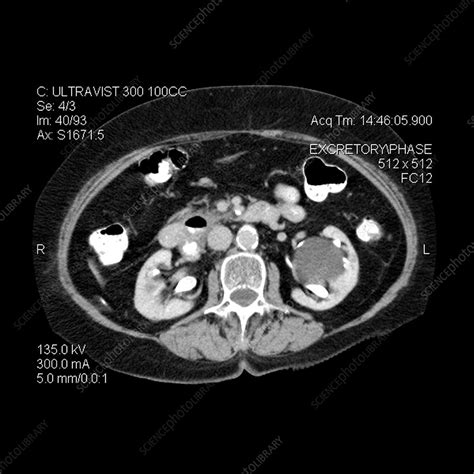

Another key analysis technique is neuroimaging, such as MRI or fMRI, which allows for direct visualization of brain structure and activity. This method is particularly useful in identifying brain abnormalities that may underlie psychiatric symptoms. For example, fMRI can show areas of the brain that are activated during specific cognitive tasks, offering a window into how different brain regions interact. Neuroimaging has proven to be instrumental in diagnosing conditions such as schizophrenia, where typical structural and functional brain differences are observed.